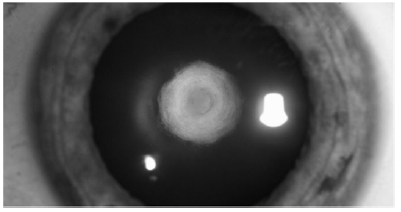

A figura acima mostra um tipo específico de catarata. Ela se caracteriza por ser unilateral (90% dos casos), podendo ter herança autossômica dominante. Considerando essas informações, assinale a alternativa que apresenta o passo da cirurgia que deve ser evitado.